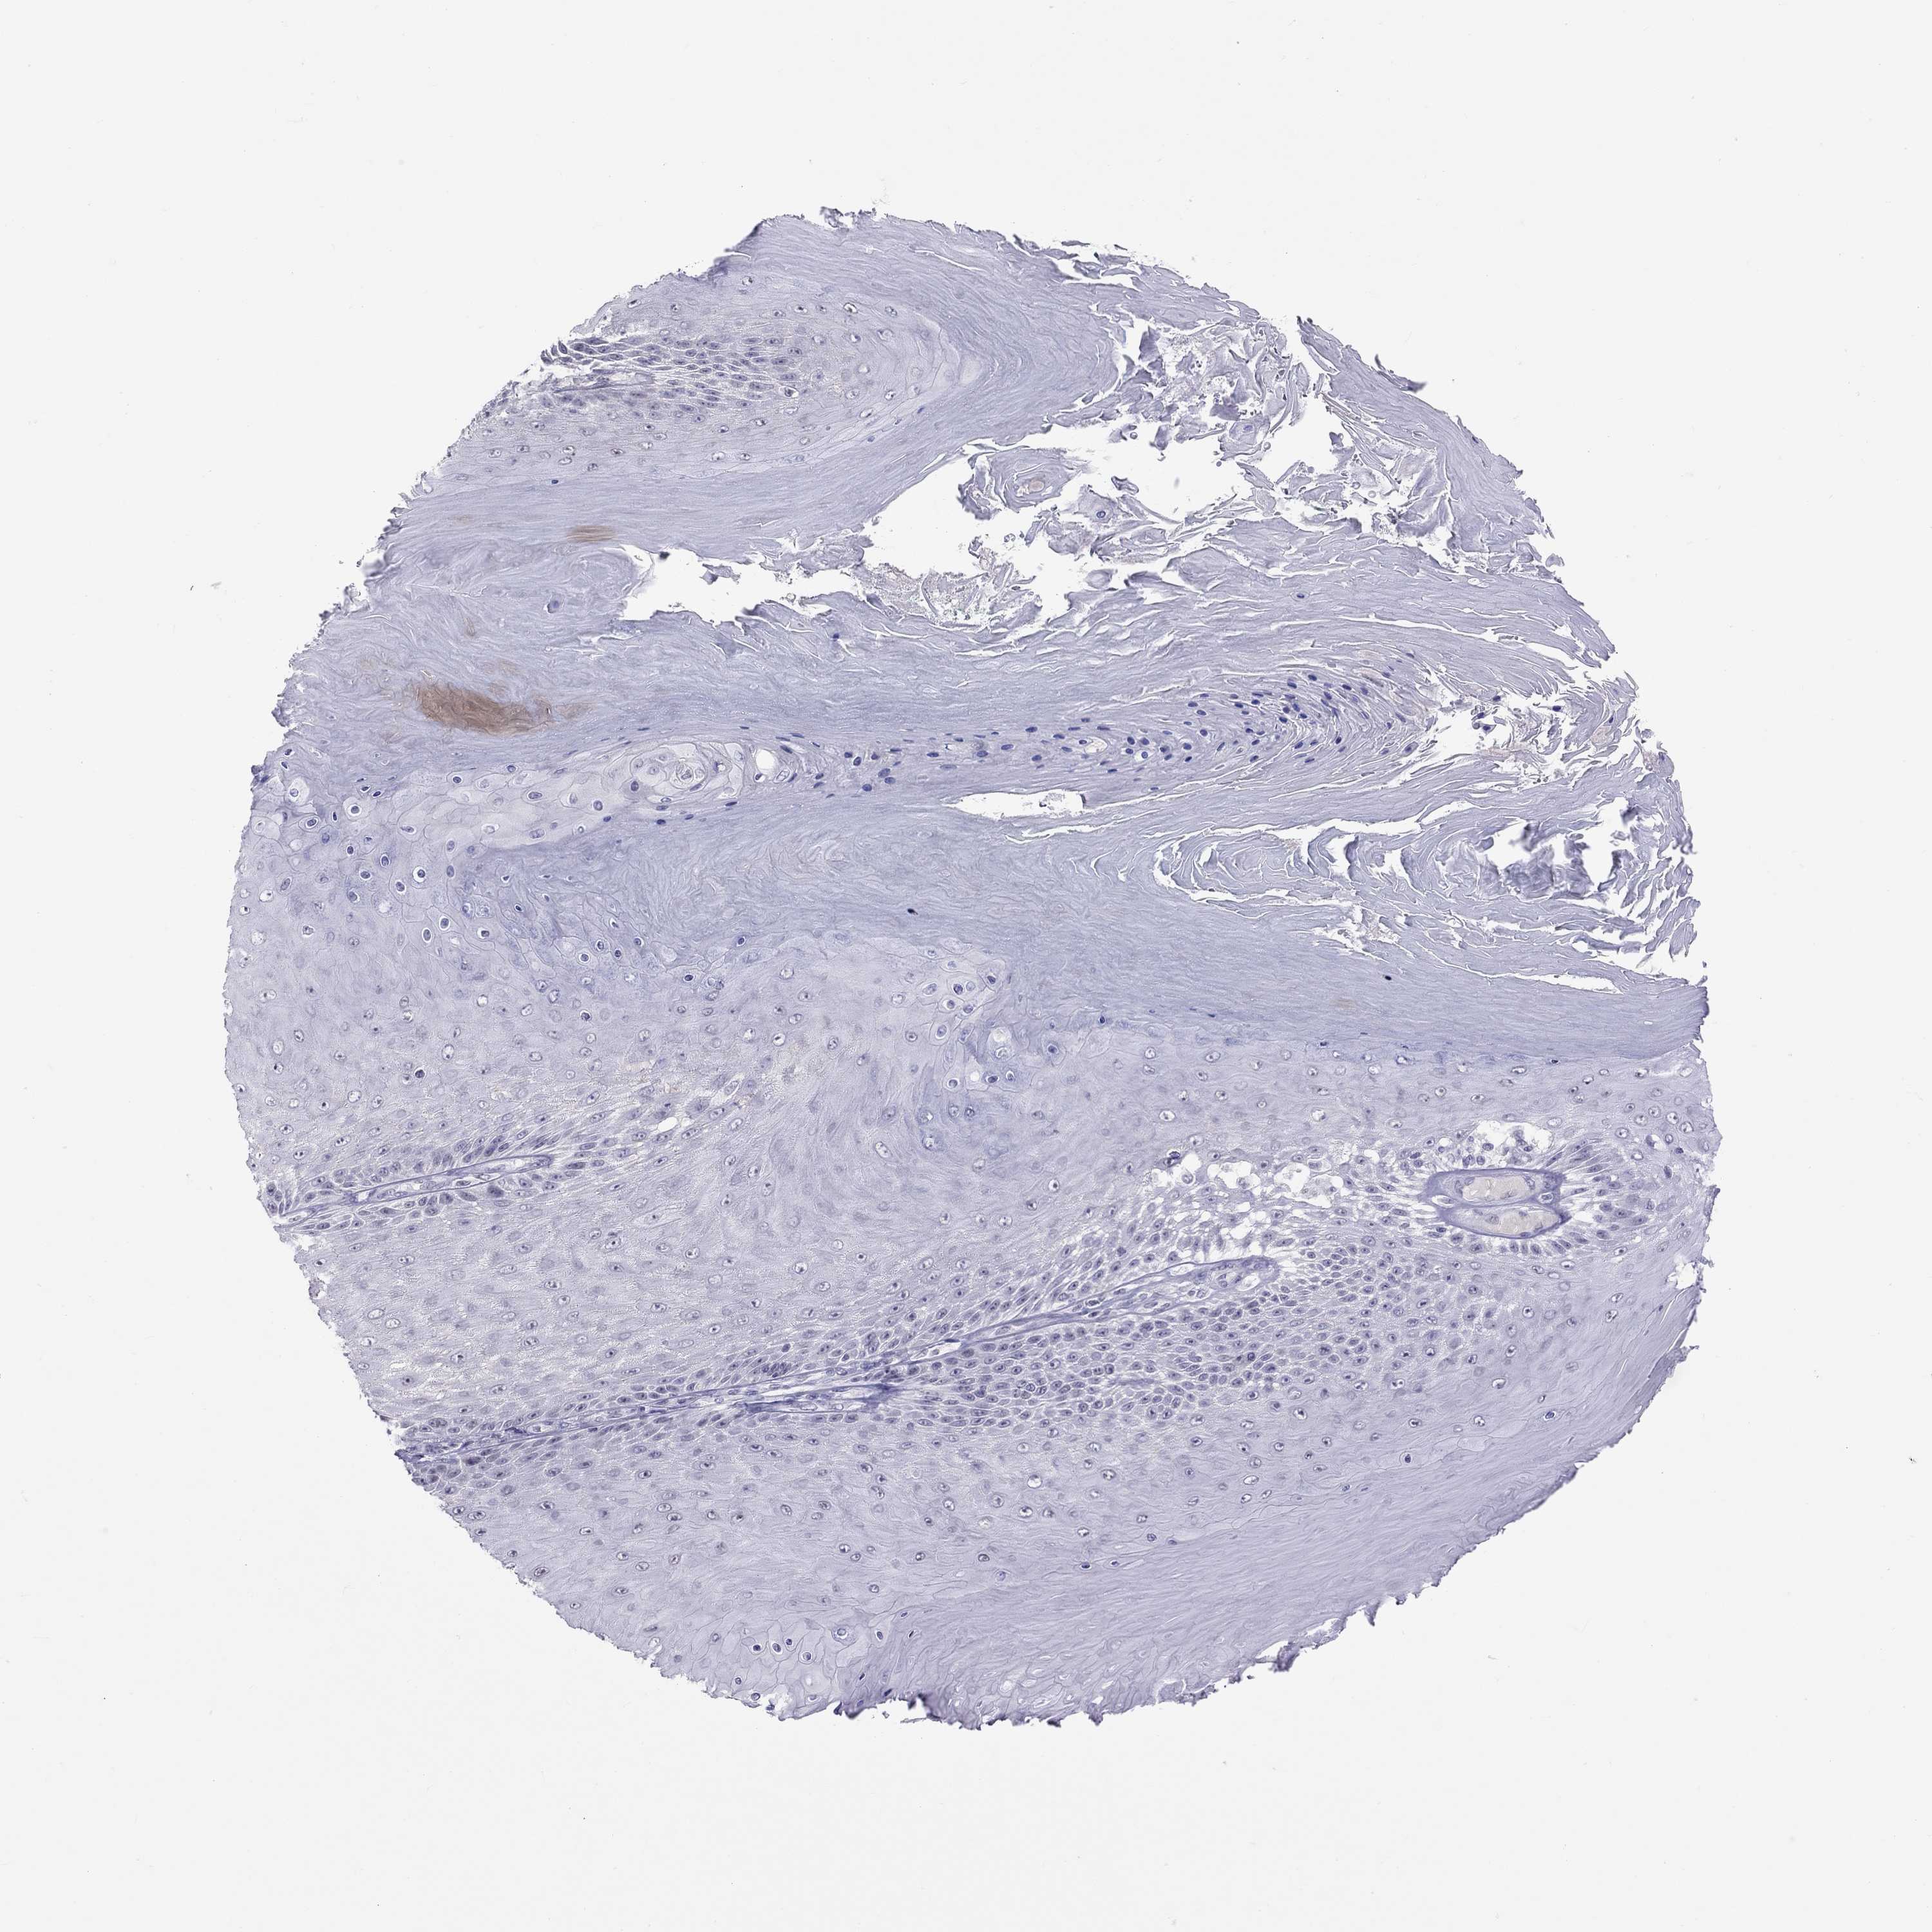

SKIN CANCER - Protein expressioni

A mouse-over function shows sample information and annotation data. Click on an image to view it in a full screen mode. Samples can be filtered based on level of antibody staining by selecting one or several of the following categories: high, medium, low and not detected. The assay and annotation is described here.

Antibody staining in the annotated cell types in the current human tissue is reported as not detected, low, medium, or high, based on conventional immunohistochemistry profiling in selected tissues. This score is based on the combination of the staining intensity and fraction of stained cells.

Each image is clickable and will lead to virtual microscopy that enables deeper exploration of all samples and also displays staining intensity scores, fraction scores and subcellular localization as well as patient and tissue information for each sample.

Antibody HPA077658

Antibody HPA077748

Basal cell carcinoma

Squamous cell carcinoma, NOS